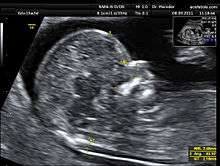

Nuchal scan

A nuchal scan or nuchal translucency (NT) scan/procedure is a sonographic prenatal screening scan (ultrasound) to detect cardiovascular abnormalities in a fetus, though altered extracellular matrix composition and limited lymphatic drainage can also be detected.[1] Since chromosomal abnormalities can result in impaired cardiovasular development, a nuchal translucency scan is used as a screening, rather than diagnostic, tool for conditions such as Down syndrome. However, increased nuchal translucency measurements are also associated with non-chromosomal abnormalities such as genetic conditions (e.g. Di George syndrome) and non-genetic ones (e.g. Body-stalk anomaly).[2] The scan is carried out at 11–13+6 weeks pregnancy and assesses the quantity of fluid collecting within the nape of the fetal neck. There are two distinct measurements – the nuchal translucency, which is measured earlier in pregnancy at the end of the first trimester, and for which there is a lower threshold for increased diameter, and the nuchal fold, which is measured towards the end of the second trimester. The scan may also help confirm both the accuracy of the pregnancy dates and the fetal viability. As nuchal translucency size increases, the chances of a chromosomal abnormality and mortality increase; 65% of the largest translucencies (>6.5mm) are due to chromosomal abnormality, while fatality is 19% at this size.[3]

Procedure

Nuchal scan (NT procedure) is performed between 11 and 14 weeks of gestation, because the accuracy is best in this period. The scan is obtained with the fetus in sagittal section and a neutral position of the fetal head (neither hyperflexed nor extended, either of which can influence the nuchal translucency thickness). The fetal image is enlarged to fill 75% of the screen, and the maximum thickness is measured, from leading edge to leading edge. It is important to distinguish the nuchal lucency from the underlying amniotic membrane.

Normal thickness depends on the crown-rump length (CRL) of the fetus. Among those fetuses whose nuchal translucency exceeds the normal values, there is a relatively high risk of significant abnormality.